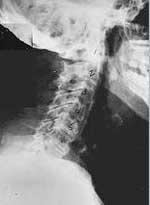

Phase One Subluxation Degeneration is seen in subluxations that have been present for up to twenty years. This phase is characterized with a loss or change in the normal curve in the spine. On this example you can see that the normal forward (lordotic) curve is lost. This spine even has developed a reverse curve in the neck. The disc spaces have also begun to exhibit a slight change in shape. One good point is that the bodies of each of the vertebrae (the square part in front) still exhibits clean clear borders. Segmental motion may be abnormal but overall motion is probably not affected. Chiropractic reconstructive care for a phase one can take from 6 to 18 months. More than 80% of people with Phase One Subluxation Degeneration have no pain. Therefore, if left uncorrected, phase one continues to progress with time until it eventually reaches the next phase.